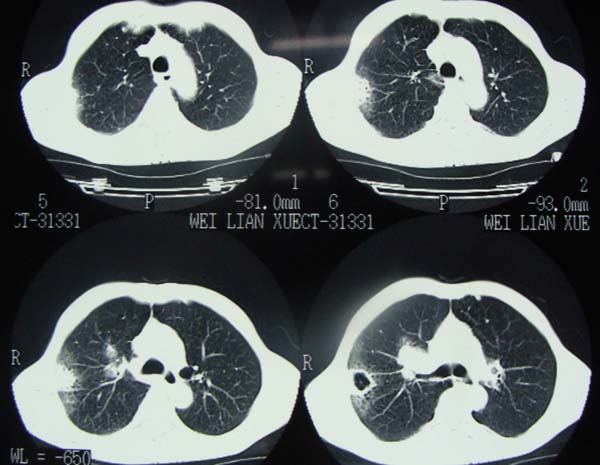

以下是引用pujunzhi在2009-6-21 21:48:00的发言:[br]右肺上叶后段见一空洞性病灶,灶周有渗出即晕征,右肺门肿大---可考虑感染性空洞和癌性空洞,先抗炎抗痨后复查并完善相关检查。有癌性空洞伴肺门淋巴结转移的可能。